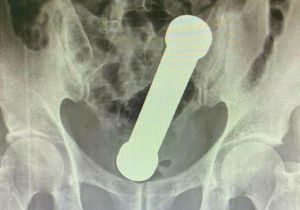

प्राइवेट पार्ट में फंस गया डंबल, डॉक्टरों ने हाथ डालकर निकाला बाहर

14 Apr, 2022 07:25 PM IST | SAMIKSHASAGAR.COMसाओ पाउलो ब्राजील के एक शख्स के प्राइवेट पार्ट (Rectum) में लोहे का एक डंबल फंस...

अपने प्राइवेट पार्ट में शख्स ने डाल लिया डंबल, एक्सरे देख डॉक्टरों के उड़े होश

13 Apr, 2022 05:36 PM IST | SAMIKSHASAGAR.COMनई दिल्ली ब्राजील से एक बेहद हैरान करने वाला मामला सामने आया है जहां डॉक्टरों की...